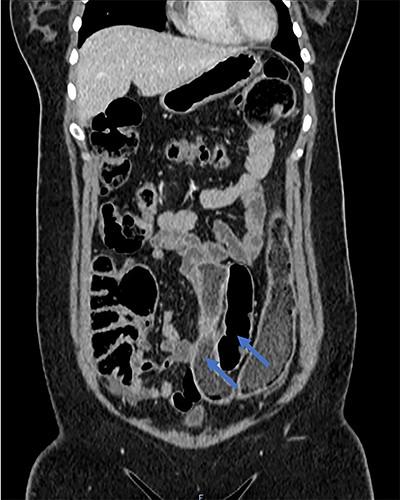

A 28-year-old woman presented to the emergency department with a 1-week history of abdominal pain, bloating and constipation. A computed tomography (CT) scan was performed, which demonstrated distension and a lead pipe appearance of the right colon suggesting a mild colitis (Fig. 1). The CT scan also demonstrated a duplicated segment of colon with a blind ending proximal limb (Figs 1 and 2), uterine didelphys (Fig. 2) and a duplicated bladder (Fig. 3). A subsequent magnetic resonance imaging scan demonstrated an 11 cm segment of thickened bowel with mucosal ulceration and surrounding hyperaemia confined to the duplicated colon. Sigmoidoscopy was performed and histology from the duplicated descending colon demonstrated mild active chronic colitis with crypt inflammation and associated abscesses without granuloma formation. The native colon had an unremarkable appearance. The patient was started on mesalazine and has had no further complaints of abdominal pain or bloating.

Coronal CT scan demonstrating native and duplicated tubular colon (indicated by blue arrows).